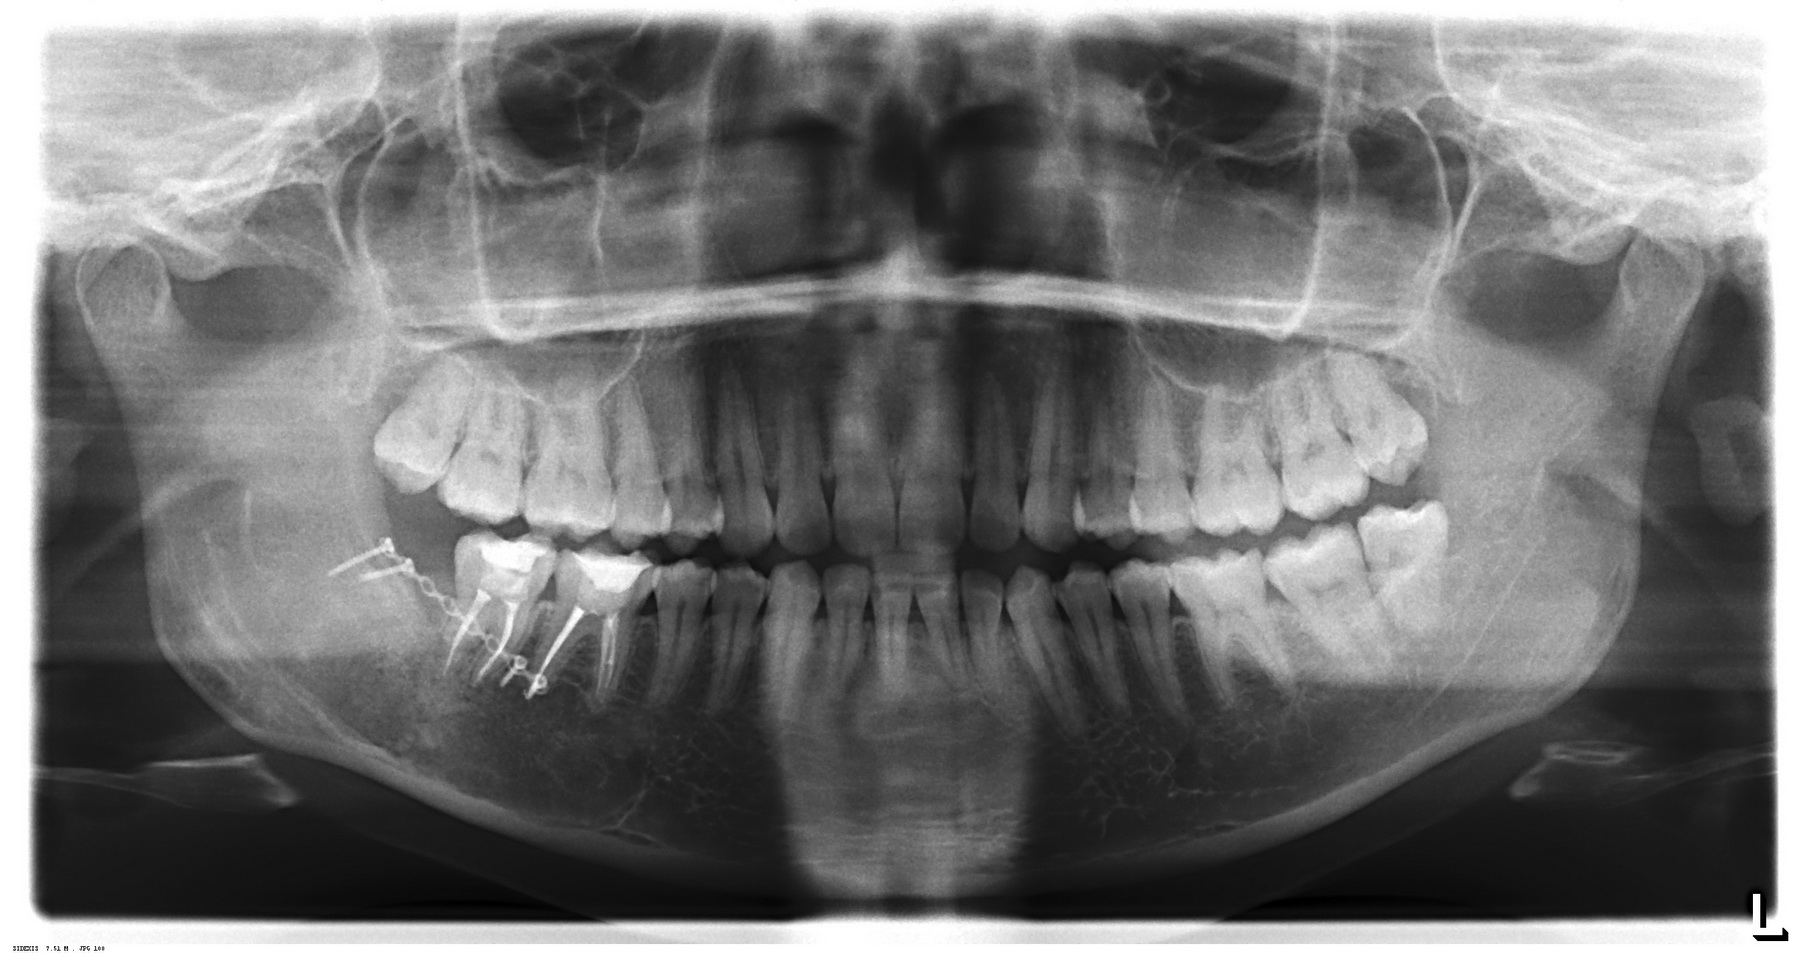

По мнению абсолютного большинства, под периимплантитом подразумевается воспалительный процесс, сопровождающийся выраженными органическими (видимыми) изменениями окружающих имплантат тканей. Чаще всего мы говорим про периимплантит, когда видим резорбцию костной ткани вокруг имплантата:

С этого момента возникает довольно серьёзная методологическая проблема: далеко не всегда деструкция костной ткани сопровождается хоть какой-то воспалительной симптоматикой. Как, например, здесь:

Снимок сделан примерно через 8 лет после имплантации. 65-летняя пациентка никакой воспалительной симптоматики не отмечает, говорит, что никогда ничего не болело и не воспалялось. Можно ли считать такой случай периимплантитом?

С одной стороны, убыль костной ткани налицо, но её причиной может быть, в том числе, обычная атрофия (всё же, возраст и состояние организма…). С другой, отсутствие каких-либо признаков воспалительного процесса в анемнезе и при объективном осмотре. Назвать этот случай периимплантитом нельзя, убыль костной ткани в этом случае вызван физиологической атрофией, связанной, в т. ч., с вышеозначенными причинами.